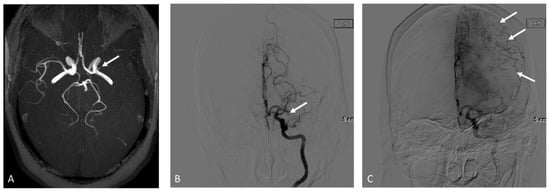

2. Materials and Methods

2.3.1. MRA

2.3.2. DSA